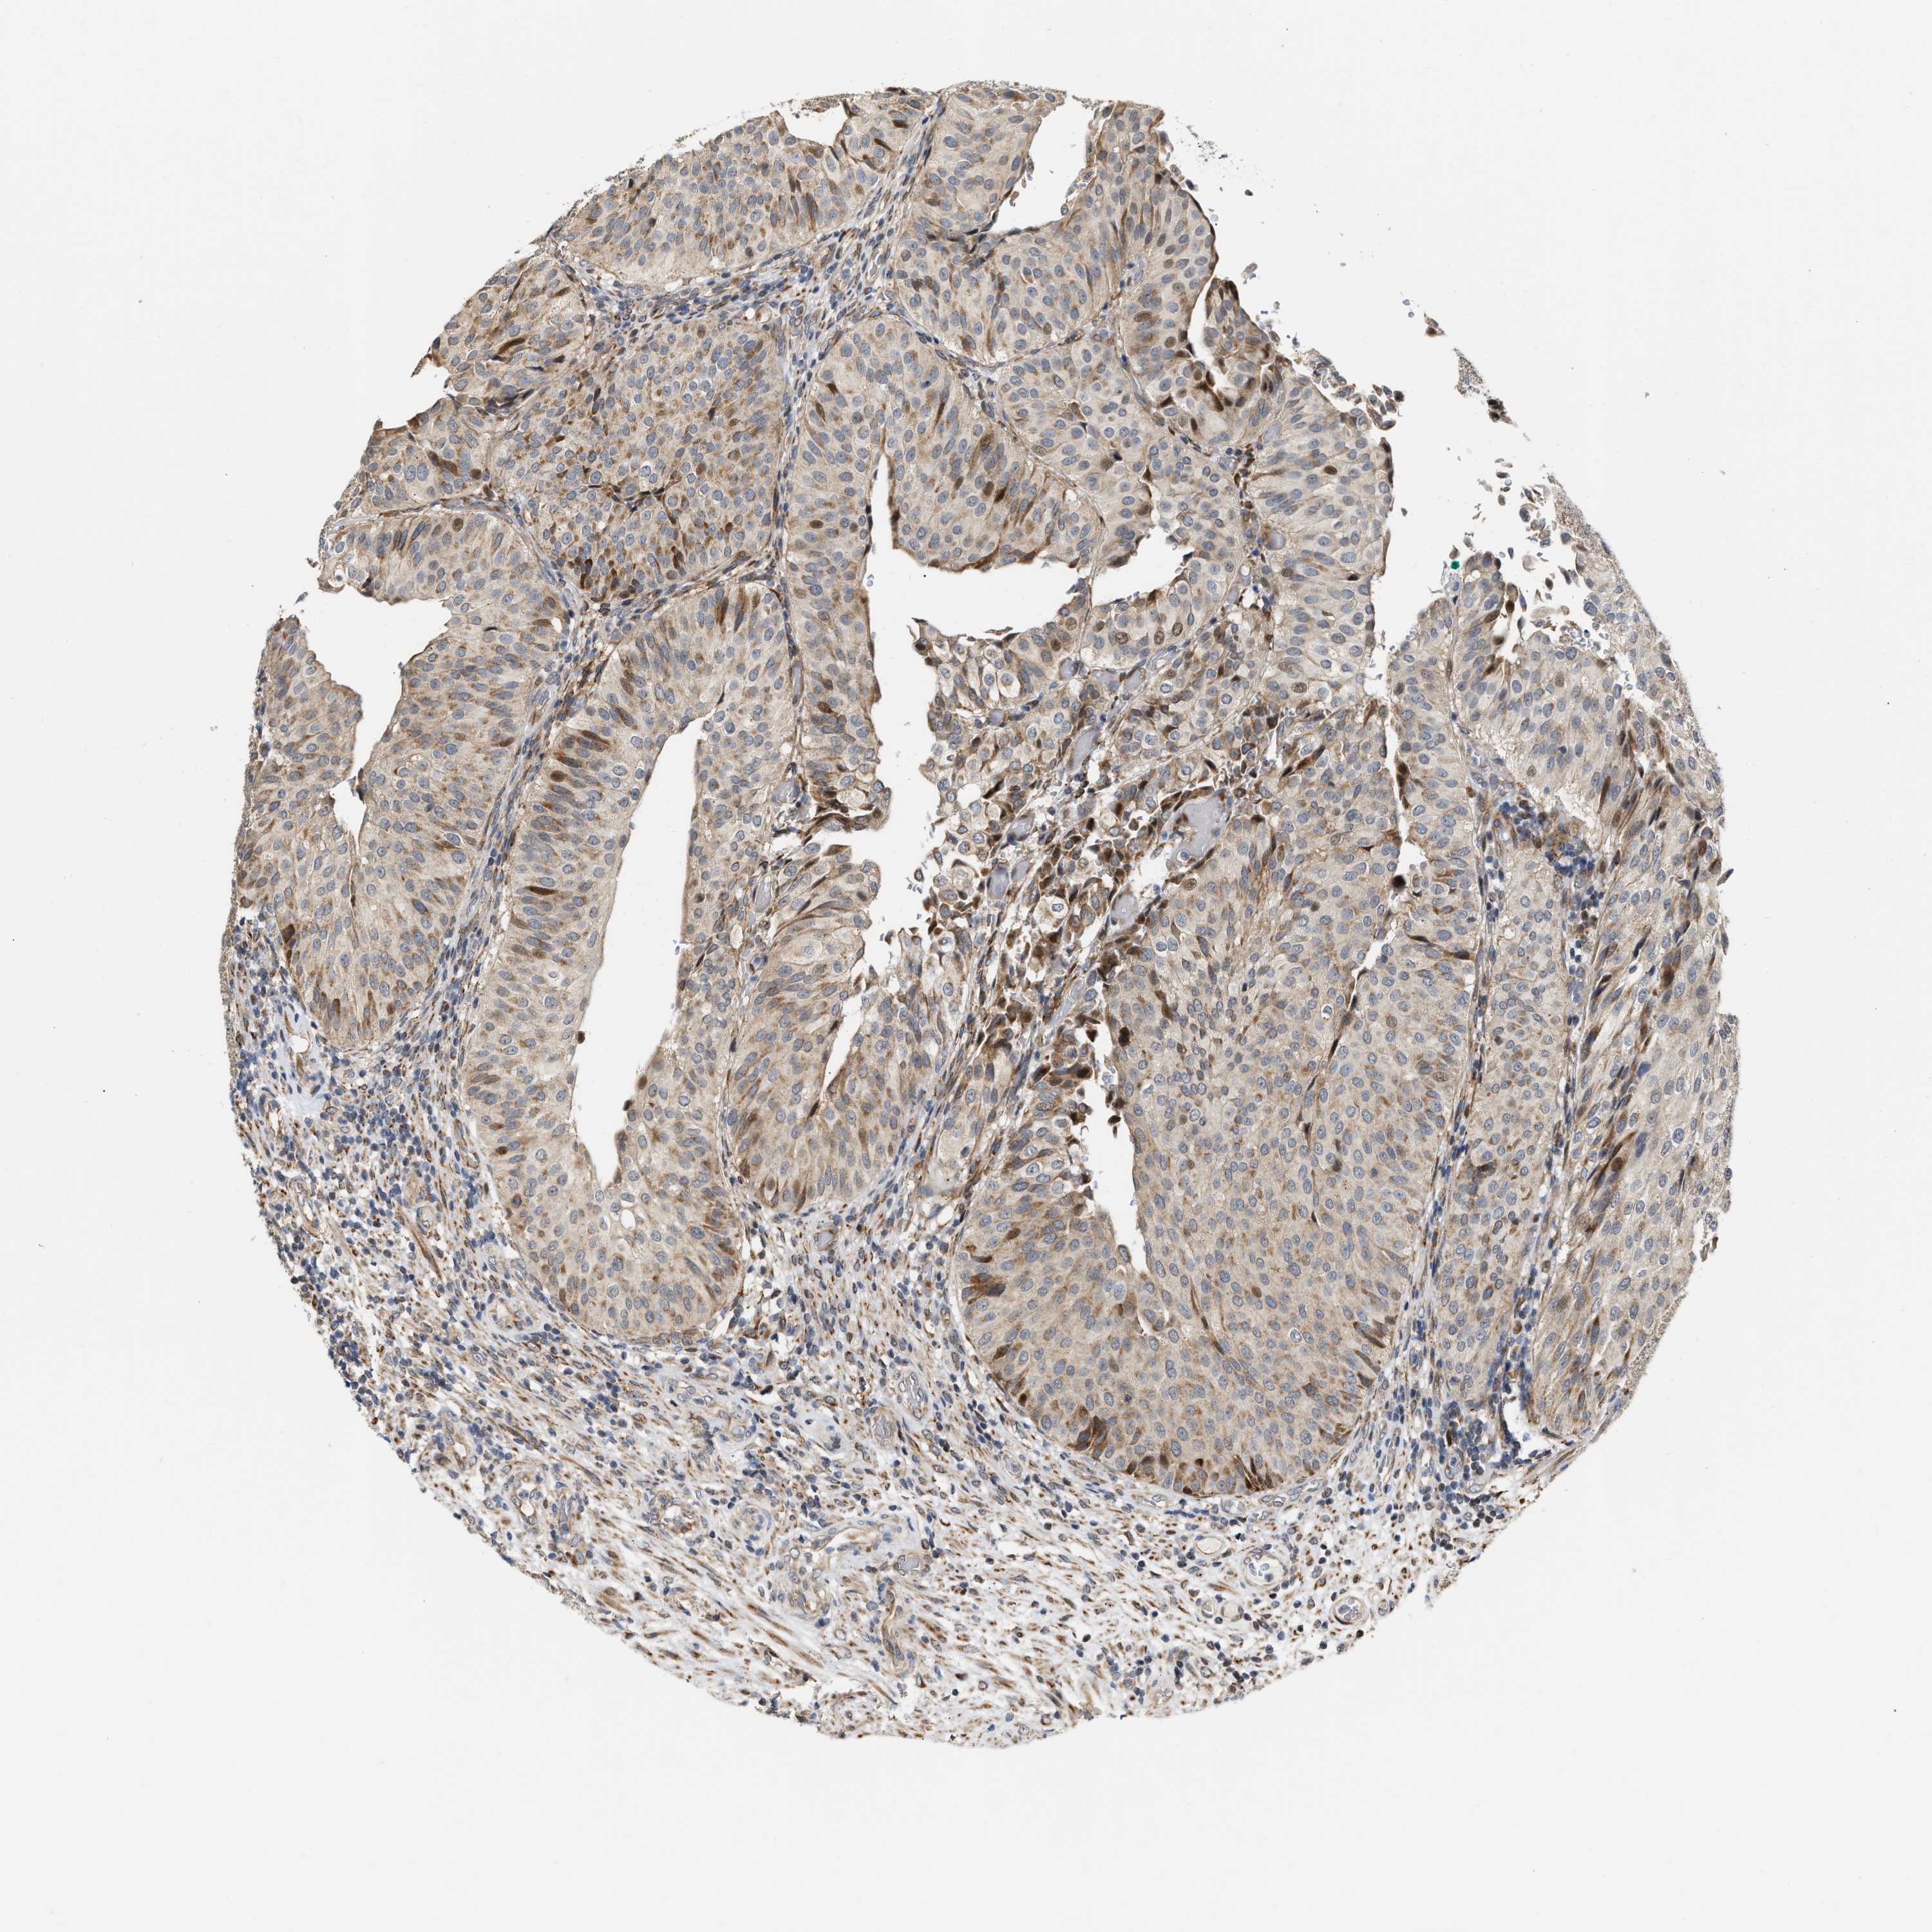

UROTHELIAL CANCER - Protein expressioni

A mouse-over function shows sample information and annotation data. Click on an image to view it in a full screen mode. Samples can be filtered based on level of antibody staining by selecting one or several of the following categories: high, medium, low and not detected. The assay and annotation is described here.

Note that samples used for immunohistochemistry by the Human Protein Atlas do not correspond to samples in the TCGA dataset.

Antibody stainingi

Antibody staining in the annotated cell types in the current human tissue is reported as not detected, low, medium, or high, based on conventional immunohistochemistry profiling in selected tissues. This score is based on the combination of the staining intensity and fraction of stained cells.

Each image is clickable and will lead to virtual microscopy that enables deeper exploration of all samples and also displays staining intensity scores, fraction scores and subcellular localization as well as patient and tissue information for each sample.

Antibody HPA023938

Antibody HPA023945

Antibody HPA024011

Antibody CAB020841

Urothelial carcinoma, High grade